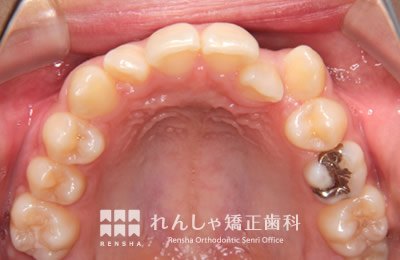

中高生

永久歯列はほぼ完成してしますが、歯列を側方だけでなく後方へも拡大し、埋まっていた右上奥歯を引っ張り出しています。

| 主訴 | 埋まったままでてこない歯がある |

|---|---|

| 診断名 | Angle Class II 小臼歯の埋伏と叢生を伴う上顎前突 |

| 初診時年齢 | 13歳5か月 |

| 装置名 | マルチブラケット装置 |

| 抜歯非抜歯 | 非抜歯 |

| 治療期間 | 2年3か月 |

| 費用の目安 | 約82万円+消費税(検査料金、都度の処置費用等も合わせた総額) |

| リスク副作用 | 歯の移動に伴う軽微な歯根吸収、歯槽骨吸収、歯肉退縮(本症例では軽度の歯根吸収を認めた)、矯正器具装着中のカリエスリスク増大(本症例ではカリエス発生無し) |